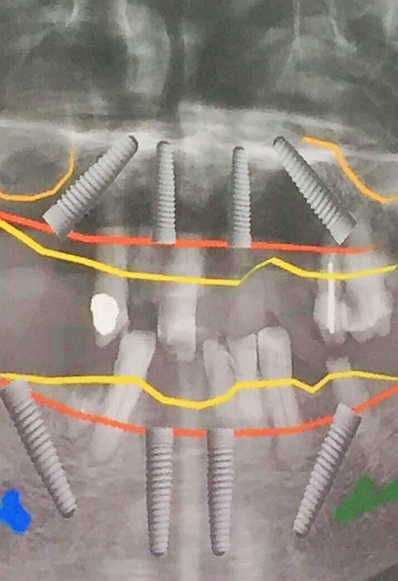

毛國(guó)斌種植病例——群討論分享